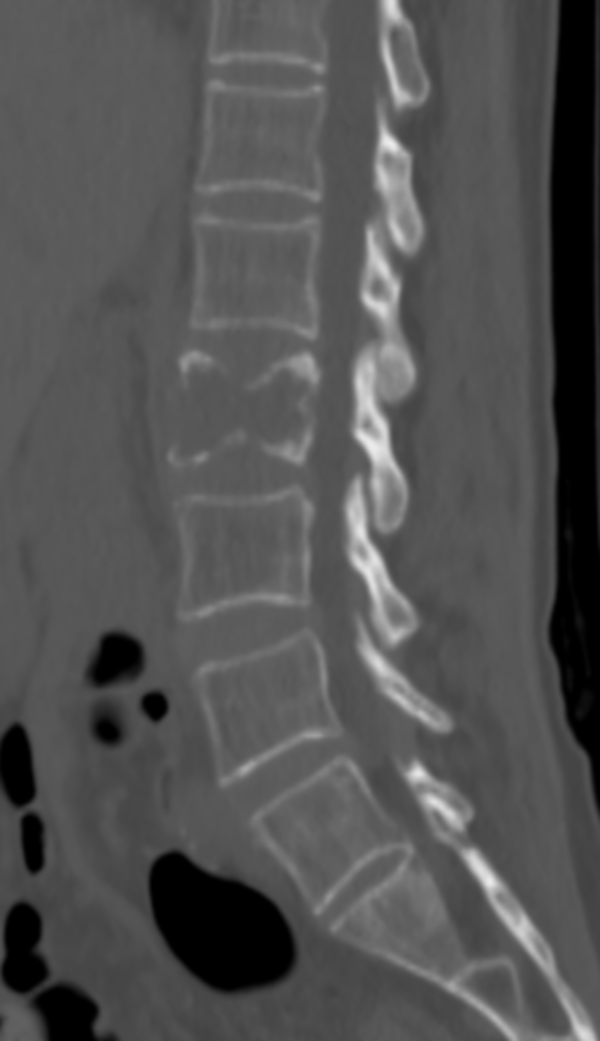

△ 术前CT:腰2椎体骨质破坏,伴周围软组织肿胀,考虑骨转移瘤。